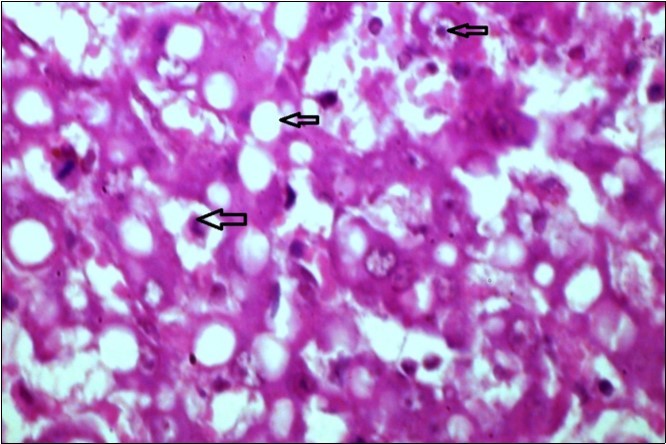

Figure 12.liver (dead cattle less than 1 year old) showed hepatocytes suffering hydropic degeneration. And necrosis (H&E, X 60).